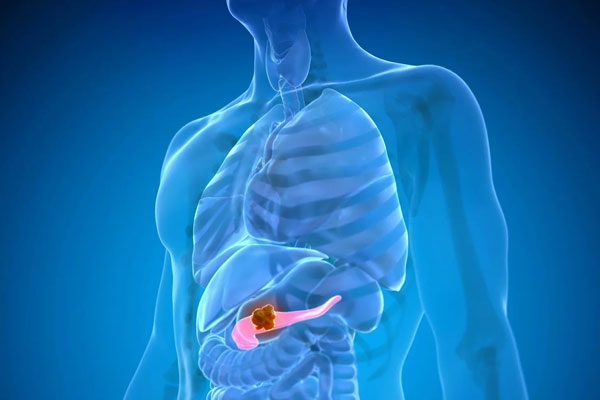

Typical indicators of pancreatic cancer include jaundice, chronic pain in the abdomen or back, pale or greasy stools, persistent constipation, profound fatigue, fever, swelling of the liver, and ongoing nausea. These symptoms are frequently dismissed, resulting in delays in both diagnosis and treatment. In the early stage, symptoms are often subtle and can go unnoticed. Individuals might face mild issues such as light-headedness, tiredness, decreased appetite, or slight discomfort in the abdomen. However, these symptoms are often misconstrued as signs of general illness, causing the disease to advance unnoticed. As the condition progresses, symptoms become more pronounced and severe. Issues like jaundice and constipation become more evident, and liver swelling may occur. The pancreas may move from its usual location, exerting pressure on surrounding organs, which can increase bile production that then enters the bloodstream, leading to jaundice. A weakening liver further raises the risks of liver failure and mortality.

At this point, the cancer has progressed to nearby blood vessels around the pancreas or perhaps four or more adjacent lymph nodes but has not metastasized to distant organs. This marks a locally advanced stage, where the cancer infiltrates neighboring tissues, complicating treatment options, although aggressive therapies can still be effective. Unfortunately, many patients only receive a diagnosis when the cancer has reached this later stage. As the disease expands beyond the pancreas into vital organs such as the liver and lungs, treatment strategies may involve chemotherapy, chemoradiation, palliative surgeries, or bypass procedures. Relying solely on medication is often inadequate, making surgical interventions essential.